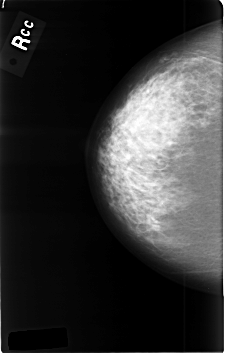

C_0362_1.RIGHT_CC

RIGHT_CC LINES 4584 PIXELS_PER_LINE 2920 BITS_PER_PIXEL 12 RESOLUTION 50 NON_OVERLAY